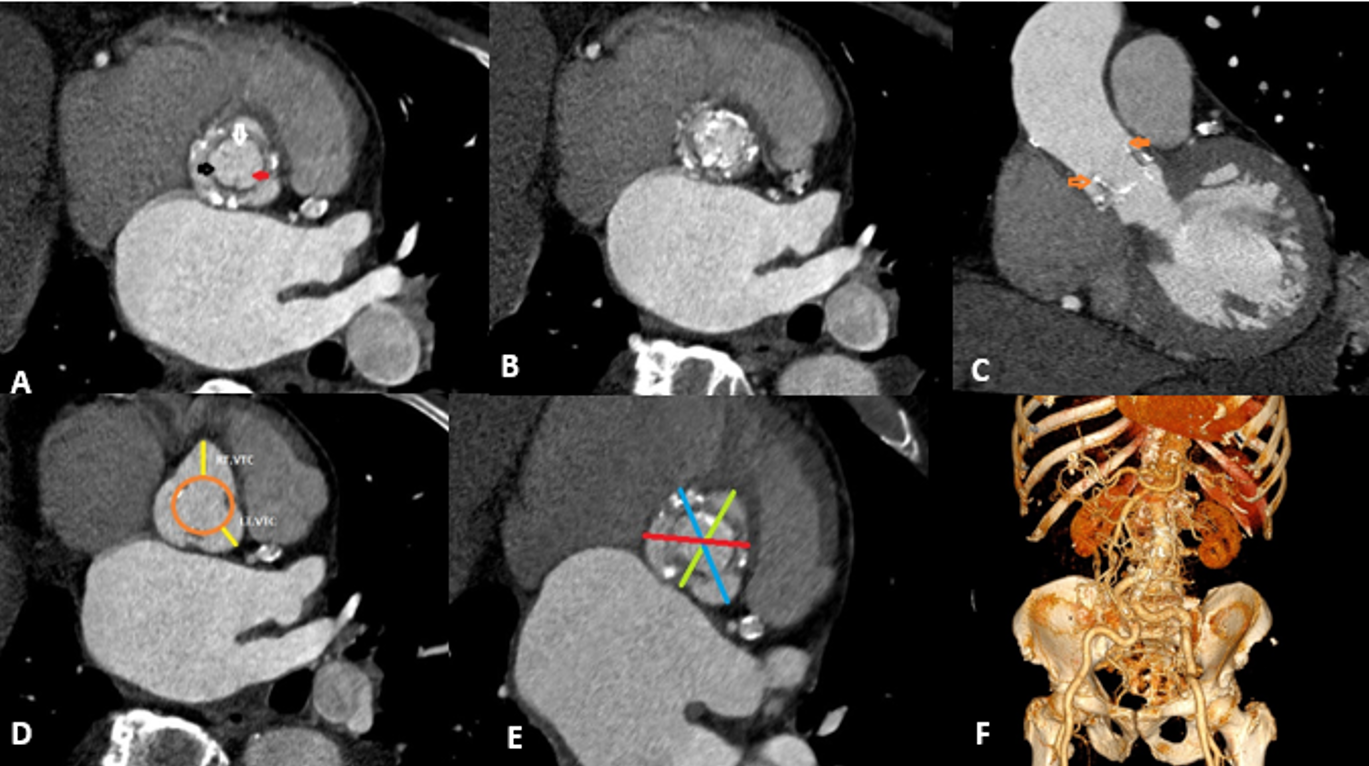

Few cases of transcatheter aortic valve implantation (TAVI) following infective endocarditis (IE) have been reported. In this presentation, we discuss the feasibility of TAVI in a degenerated bioprosthetic valve affected by IE.

We examine a rare case involving an elderly man with a degenerated bioprosthetic aortic valve complicated by IE 6 months after a COVID-19 infection. The patient was successfully treated with valve-in-valve intervention following antibiotic therapy for the acute phase of the infection. This resulted in excellent outcomes with no complications in the early postprocedural period and during follow-up visits.

For patients with a destructed bioprosthetic aortic valve due to IE and residual dysfunction after healing, valve-in-valve intervention can be a safe and effective treatment option, particularly for those at high risk for surgery.